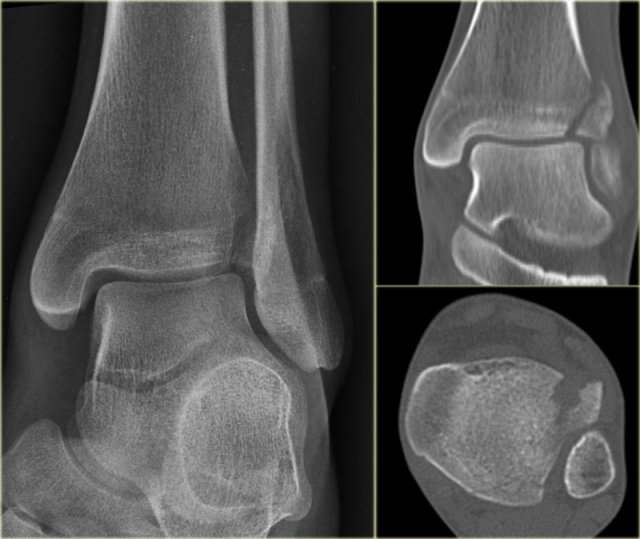

In some cases a fracture of the posterior malleolus is barely or not visible on the radiographs and can only be seen on CT.

First study the radiographs and then continue with the CT.

By the way....there are two fractures.

You can enlarge the images by clicking on them.

The CT shows an avulsion of the tertius at the insertion of the posterior syndesmosis (red arrows).

The alignment is so perfect, that you do not see the fracture on the radiographs.

Maybe the fracture is seen on the AP-view as indicated by the red arrows, but this is questionable.

Notice that there is also an avulsion at the tibial insertion of the anterior syndesmosis, i.e. Tillaux fracture.

This combination of findings implicate that the ankle is unstable.

A syndesmotic screw has to be inserted.